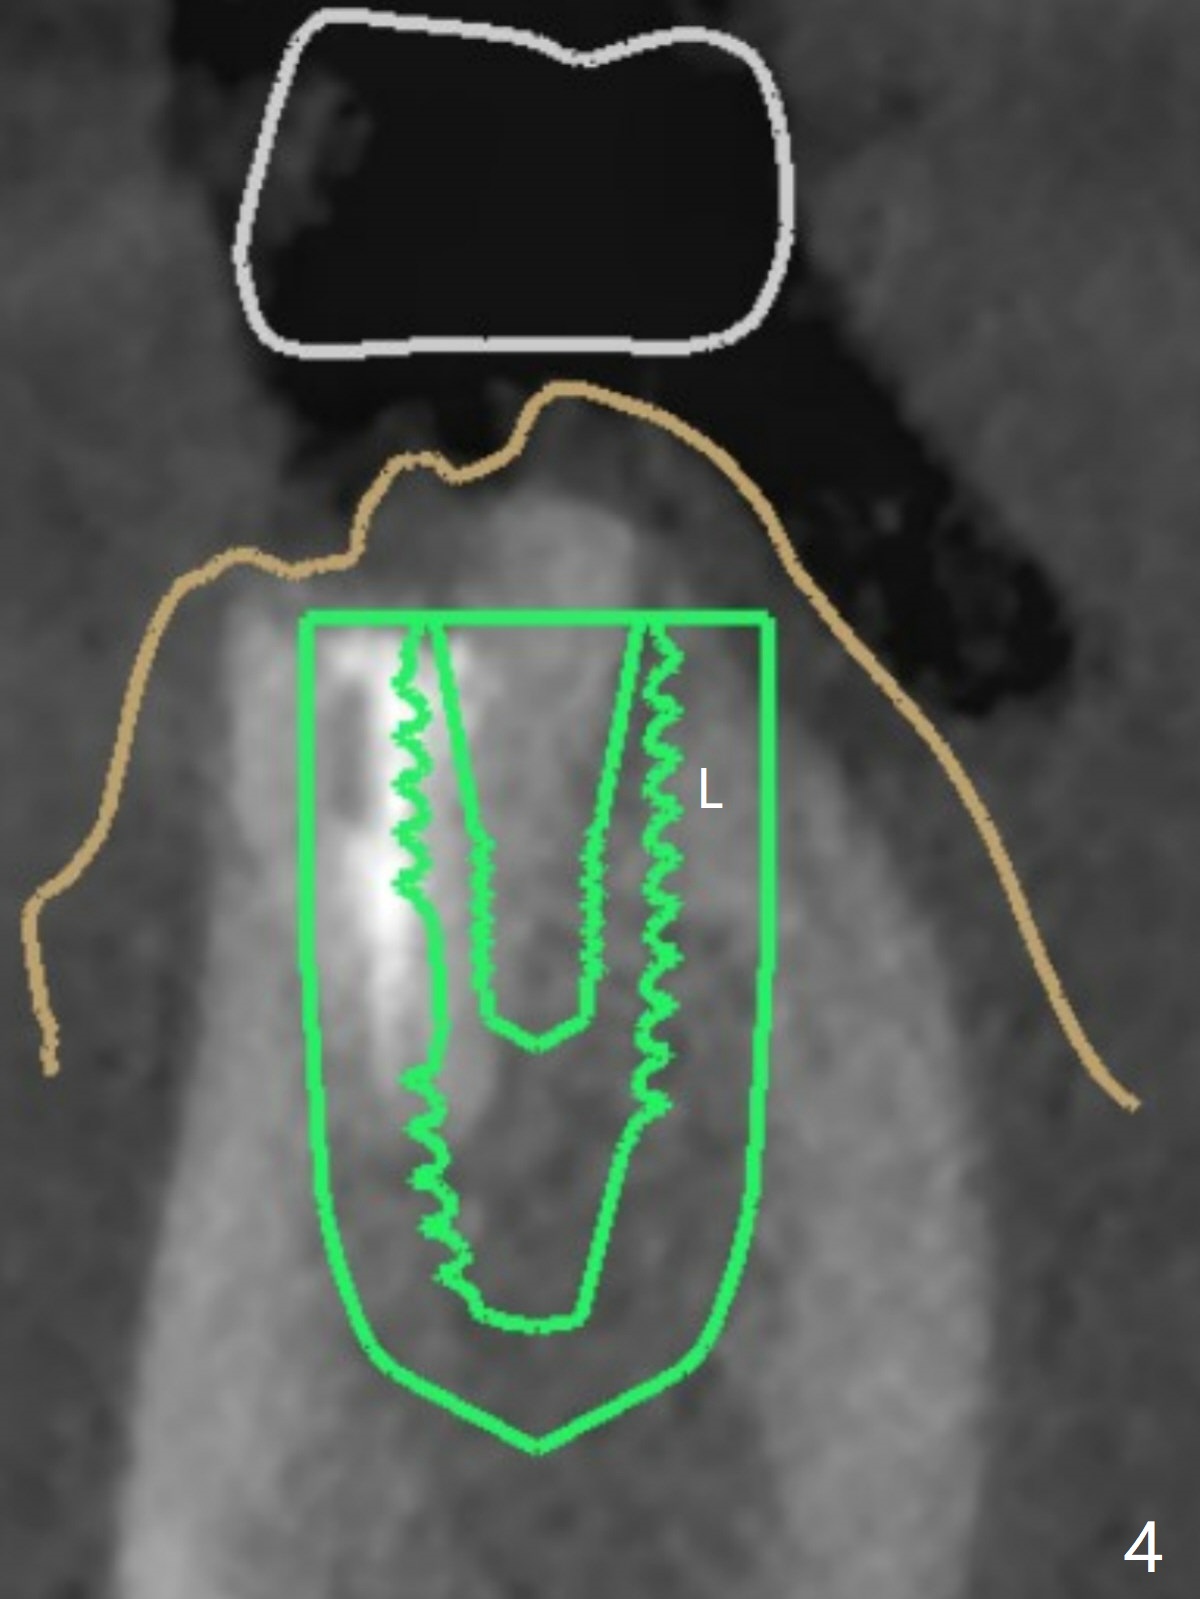

为了预防钻头遇到舌侧骨板而往颊侧偏移,有意不拔除第二前磨牙牙根。但是2.2毫米钻头钻洞很吃力,最后不得不拔除牙根,阻力骤然减少,顺利完成植入,而且颊侧间隙还够(图一,二),填入骨粉后远中螺纹间空间消失(图三箭头)。今后最后一个钻头完成钻洞后留在原位,周围放置适当量的骨粉,然后取出钻头,植入植体,这样空间可以比较全面充填。即刻种植没有颊侧偏移可能是因为设计时植体没有过多接触舌侧骨板(图四L)。第二磨牙延期种植需要切开是因为颊侧角化牙龈不足。术后两个月,前磨牙植体顶端似乎被牙槽嵴覆盖了(图五 *)。术后五个月,旋转7愈合基台,下面植体疼痛,可能与植体螺纹断裂有关(图六:>),5取模。